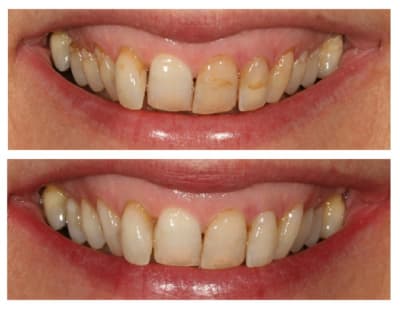

cette patiente que je suis en controle depuis 2 ans, se décide à faire quelque chose pour son sourire.

grosso modo depuis 2 ans, pas de soucis particuliers, pas de caries, faut faire un peu gaffe à la paro mais elle est plutôt motivée et ça se passe bien.

elle a plein de vieux compos d'une mauvaise couleur, au joints colorés, des dents de couleur pas vraiment toutes pareilles ; et un sourire très gingival.

je ne sais pas trop d'ou ça viens, de mylolyses traitées au compo ou d'un épisode de caries au collet ?

elle ne fume pas, bois du thé, un peu de café.

Si on regarde la photo 3, sourire de face, tu doit faire 10 céram en haut, de

5 à 5 (et là, je ne retiens pour pas dire 12...)

Ensuite, tu fais rien pour la couleur en bas ? OK

pour l'attrition ? OK, au pire une goutière nocturne.

Si tu touches 6 dents (3 à 3), ben le sourire ne sera tjs pas trop beau...juste mon pt de vue.

13/07/2011 à 22h44

merci à ceux qui ont participé, vous m'avez fait penser à des choses que je n'avais pas imaginé pour le traitement de ma patiente

et effectivement, si on avait voulu faire un sourire parfait, on aurait pu faire ortho, alignement des collets, facettes, voire une chirurgie de la lèvre pour le sourire gingival

la patiente n'est pas du tout venue pour ça, et je ne me vois pas lancer tout ça pour une patiente qui ne se plaint que de ses composites et un peu de sa 12

je lui ai proposé un éclaircissement, de refaire les compos, et de voir après si on pouvait rentrer la 12 avec un moyen ortho amovible (invisalign, inman aligner ou autre)

puisqu'elle a refusé tout net les bagues

je n'avais pas pensé à corriger sa classe II, ni a tout couronner ou facetter pour "ressortir" les dents très rentrées ; ni même a aligner ses collets en fait.

pour cette patiente qui n'avait pas de grandes exigences, je me suis auto limité en voulant être le moins iatrogène possible.

comme quoi poster m'aura été utile, j'avais pas tout vu ni tout envisagé.

je reste content de mon traitement, tout simplement parce que la patiente est très contente.

elle n'a même pas eu envie d'essayer de bouger la 12 après (et tant mieux parce que maintenant qu'on en a discuté, ça aurait surement été galère de ne toucher que ça)